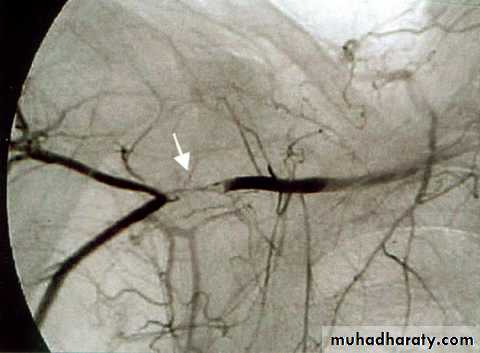

Angiography of hand vessels